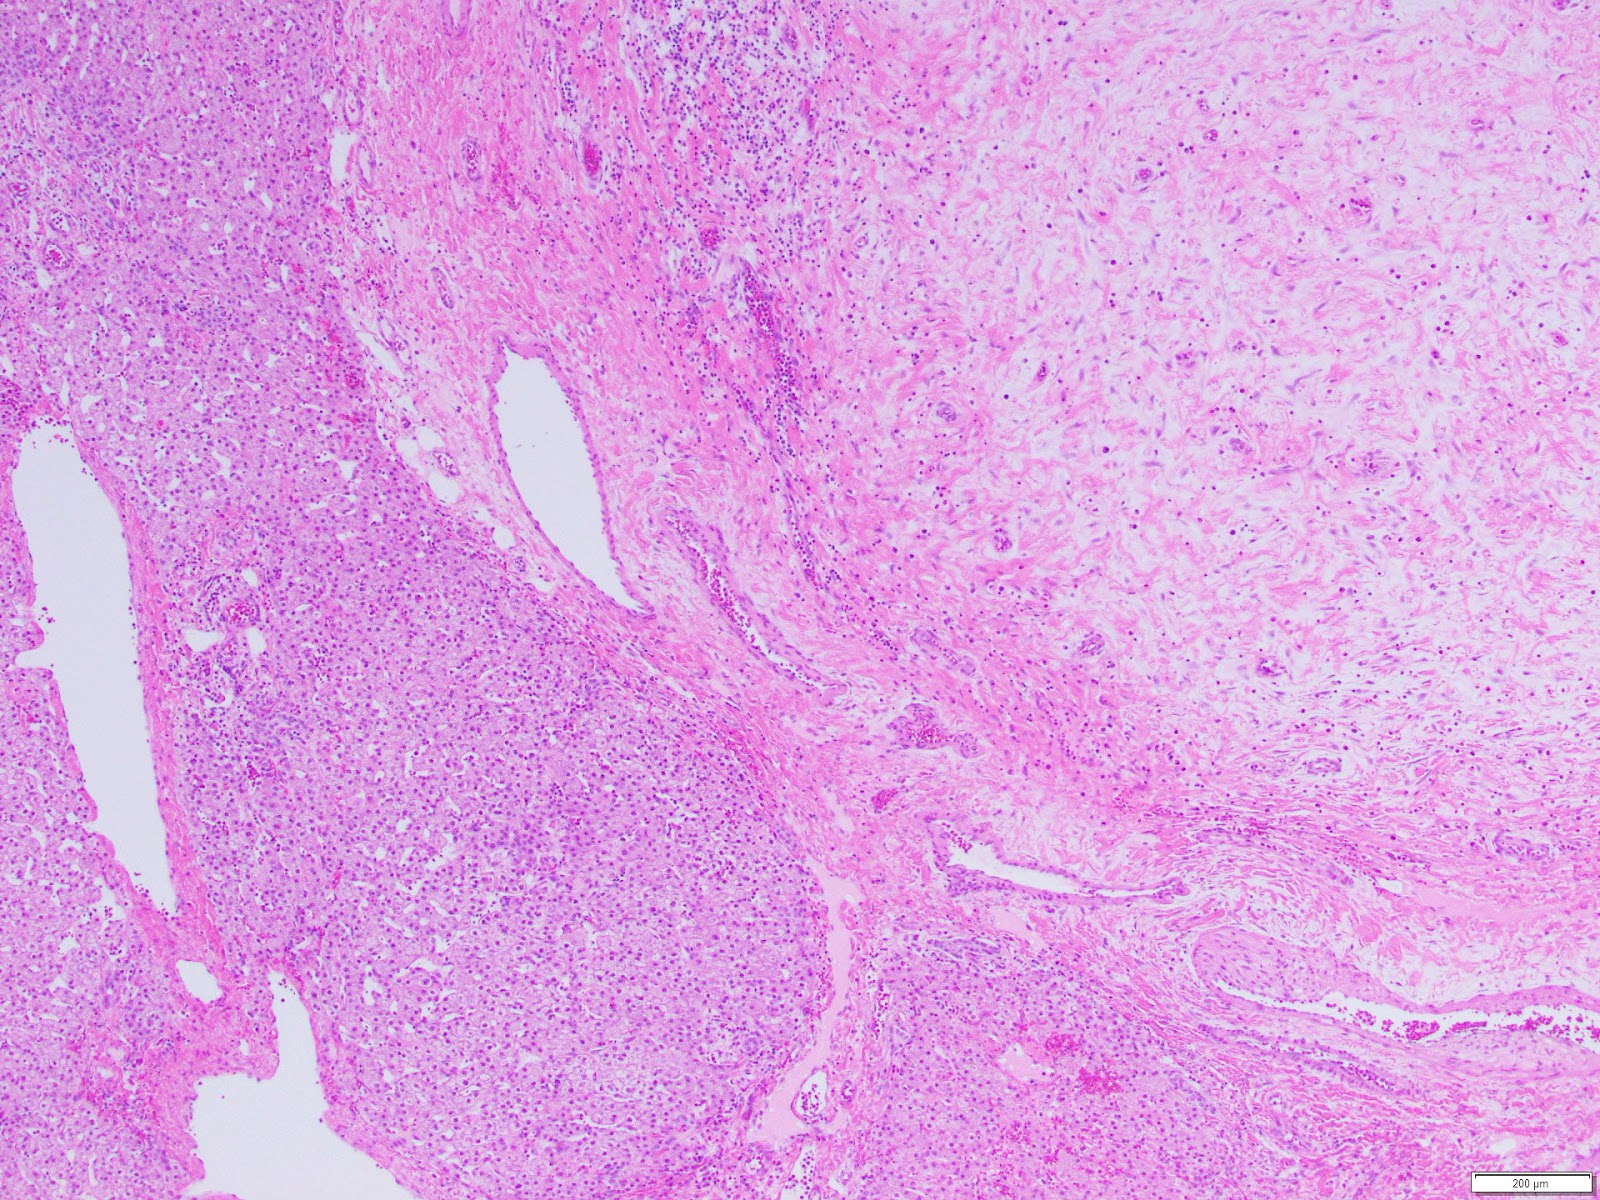

The patient underwent partial liver resection and gross examination showed an 18 x 17 x 5 cm, pink-purple cystic lesion. The cut surfaces were gray-white to pink-yellow with numerous cystic spaces up to 13.5 cm in greatest dimension and cross-sections revealing smaller intramural cysts (Figures 3 and 4). A portion of the specimen was sent for cytogenetic analysis, which failed due to lack of metaphase spreads. Microscopic examination revealed that the lesion was composed of a bland spindle cell population (Figure 5) within a variably loose, edematous, myxoid to hyalinized stroma with scattered ectatic thin-walled vessels, and occasional entrapped large biliary structures, the latter surrounded by dense concentric fibrosis (Figure 6). Grossly appreciated cystic structures were not lined by epithelium, and contained degenerated blood or bile (Figure 7), the latter often with xanthomatous reaction at the periphery (Figure 8). Cords of benign hepatocytes were prominent at the periphery of the lesion (Figure 9).